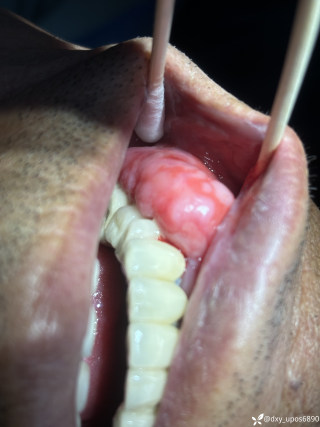

病例信息【患者信息】:男、16岁【主诉】:全身皮肤瘙痒伴皮疹10分钟【现病史及既往史】:10分钟前患者骑摩托车行驶途中,突感全身瘙痒,奇痒无比伴全身发热,心跳加快。急诊就诊,既往无类似病史,否认咽喉梗阻感、胸闷、气短、呼吸困难、恶心、呕吐、腹泻、乏力等不适。【检查】:血压:138/80mmHg,心率:116次/分,呼吸:21次/分。【临床诊断】:急性荨麻疹【治疗经过及结果】:给予吸氧、肌注扑尔敏1支,口服氯雷他定1片,静滴甲泼尼龙40mg后瘙痒明显减退,皮疹消失。病例讨论双手十指及双足未纹身,护士最后穿刺左手大拇指。